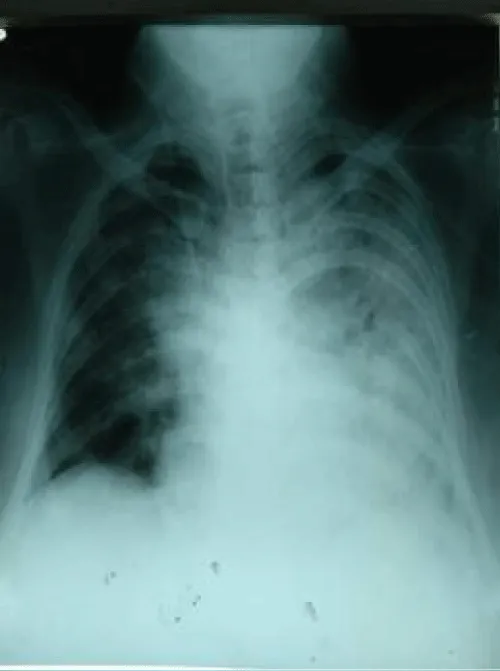

A-91-year old man had fever, cough with dyspnoea for 7 days and was brought to hospital. He was previously healthy and lived with caring family. He did not have dementia and was ambulating well. He was not diabetics nor hypertensive. His nasopharyngeal swab for Covid-19 PCR was positive. His SaO2 on air was 83% and respiratory rate was 28/minutes. Chest Xray was consistent with severe pneumonia as patchy opacities occupied more than 50% of lung parenchyma on both sides (Figure 1(a)). His total WBC was 31.6 X109/l and absolute lymphocyte count was 2.2 X109/l. He had high LDH (1262 U/L), high CRP (297.94 mg/l) and serum creatinine was marginally raised (1.6 mg%) Thus, he was treated as a case of severe Covid-19 infection with oxygen 10L/min, imipenem, azithromycin, dexamethasone, low molecular weight heparin, vitamins and dexamethasone. Convalescent plasma therapy was given on Day 12 symptom onset.

He made gradual improvement over one weeks. His symptoms improved on Day 14 symptom onset. Absolute lymphocyte count decreased to 1.5 X 109/l and Chest Xray too (Figure 1(b)). His nasopharyngeal swab for Covid-19 PCR was negative on Day 15 symptom onset.